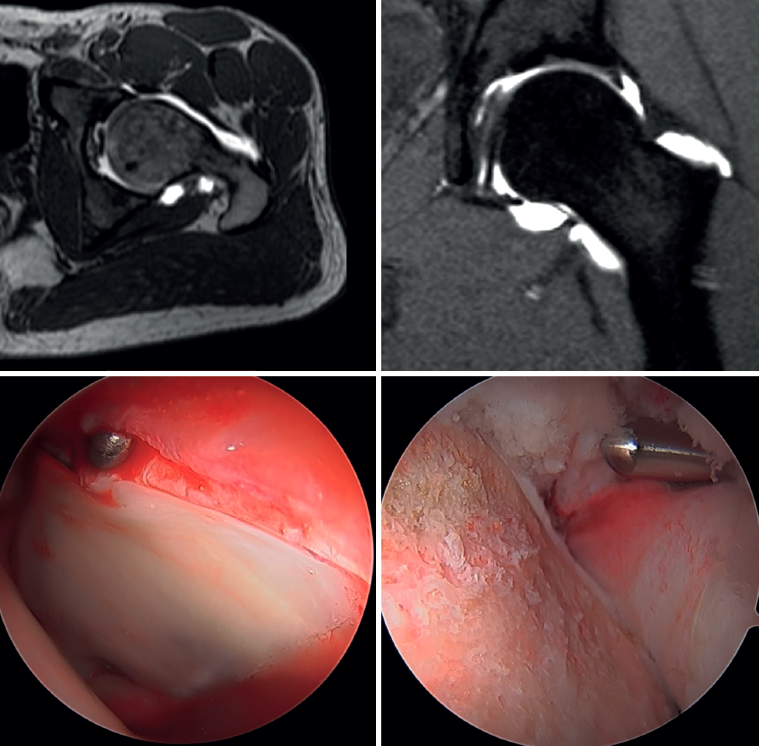

All surgeries were performed in the supine position and on a traction table with perineal post. The anterolateral, mid-anterior and distal anterolateral portals were used. In order to be able to perform the necessary procedures in each patient, an interportal capsulotomy was used in all cases in the central compartment (bony treatment of the acetabular rim, debridement of chondral lesions to secure stable edges, microfractures, labral debridement or repair), except in young women with signs of joint hyperlaxity, in which case independent capsulotomies were used (Figure 1). In patients with cam-type deformities (alpha angle >55°), a T-capsulotomy (with different edge traction systems, and only in those patients with difficult access to the femoral bump) was performed to gain access to the peripheral compartment and resect the femoral deformity until an adequate head-neck transition was achieved to prevent conflicts of space, tested by intraoperative dynamic examination to confirm adequate correction (Figure 2). The intraoperative procedures made are described in Table 1.